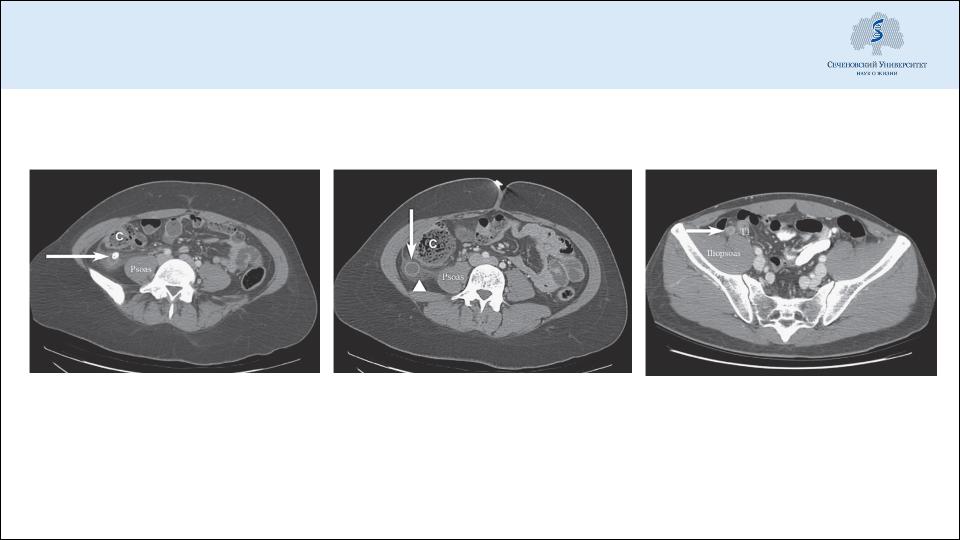

Компьютерная томография

Копролит в просвете

Червеобразный отросток

Утолщение стенок червеобразного

червеобразного отростка

увеличенного диаметра, экссудат

отростка при воспалении